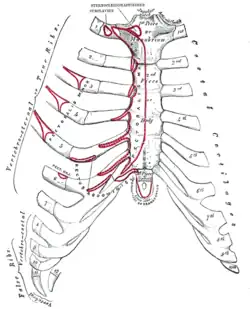

The human rib cage (Source: Gray's Anatomy of the Human Body, 20th ed. 1918.) | |

Protection on the rib cage of the heart, lungs and diaphragm. The shaded areas indicate the extent of the pleural cavities not filled by the lungs. | |